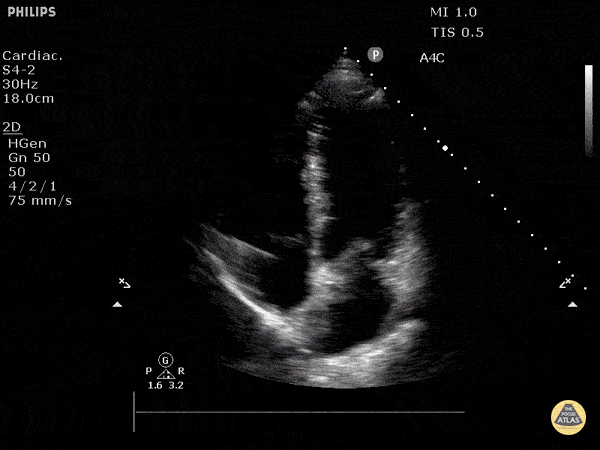

Normal Cardiac Anatomy - Normal Apical 4 Chamber